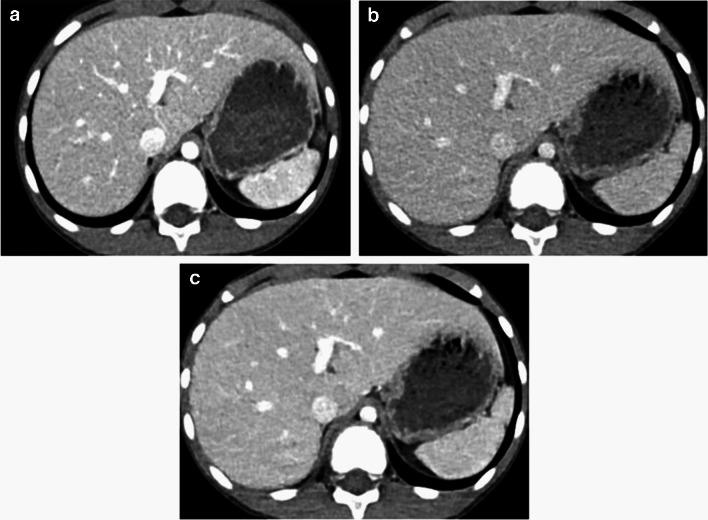

The standard-dose group exhibited higher attenuation, contrast-to-noise ratio (CNR), and signal-to-noise ratio (SNR) of organs and vessels compared to the low-dose group (all P-values < 0.05 except for liver SNR, P = 0.12). However, noise levels did not differ between the standard- and low-dose groups (P = 0.86). The contrast-boosted group had increased attenuation, CNR, and SNR of organs and vessels, and reduced noise compared with the low-dose group (all P < 0.05). The contrast-boosted group showed no differences in attenuation, CNR, and SNR of organs and vessels (all P > 0.05), and lower noise (P = 0.002), than the standard-dose group. In qualitative analysis, the contrast-boosted group did not differ regarding vessel enhancement and lesion conspicuity (P > 0.05) but had lower noise (P < 0.05) and higher organ enhancement and artifacts (all P < 0.05) than the standard-dose group. While iodine uptake was significantly reduced in low-iodine-dose CT (P < 0.001), there was no difference in radiation dose between standard- and low-iodine-dose CT (all P > 0.05).

Low-iodine-dose abdominal CT, combined with an AI-based contrast-boosting technique exhibited comparable organ and vessel enhancement, as well as lesion conspicuity compared to standard-iodine-dose CT in children. Moreover, image noise decreased in the contrast-boosted group, albeit with an increase in artifacts.

结果

与儿童标准碘剂量CT相比,低碘剂量腹部CT联合基于AI的造影剂增强技术在器官和血管强化以及病变清晰度方面表现相当。此外,造影剂增强组的图像噪声降低,尽管伪影有所增加。